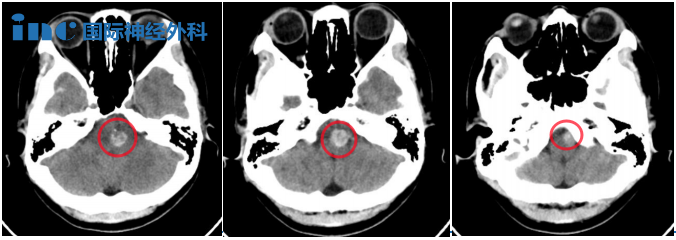

2023年11月琳琳头颅CT